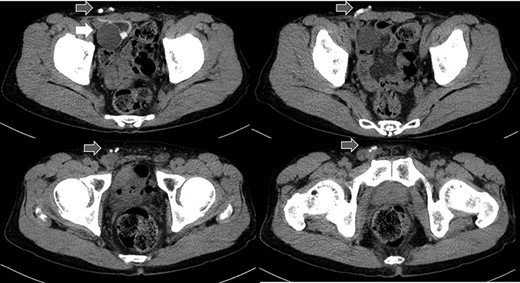

A 75-year-old male was referred for the treatment of a right IH. He also had received AUS implantation for a similar medical course. Abdominal CT demonstrated that a balloon was located beside the bladder and that the connecting catheter went through the rectus abdominis muscle and reached to the right scrotum through the subcutaneous layer (Fig. 5). The catheter was palpable subcutaneously; therefore, skin incision was placed on the outer site rather than in the normal situation. The diagnosis was indirect hernia and we did not observe any components of the AUS in the inguinal canal and repaired it using the Lichtenstein method.

Abdominal CT in Case 2: the balloon was located near the bladder and the tube went through rectus abdominis muscle; balloon, white arrow; tubes, gray arrows.